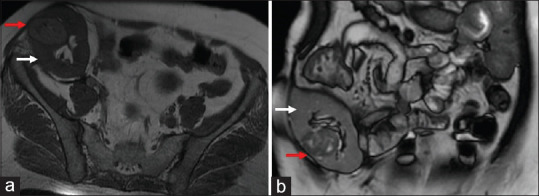

我们报告了我们在同种异体移植肾中完全内生的小肾肿块的保留肾脏手术的经验。37岁女性,因月牙状肾小球肾炎终末期肾病接受活体肾移植术后14年,表现为3.6 cm肾肿块。患者行开放性同种异体肾部分切除术,术后第5天出院。术后6个月移植物功能良好,肿瘤无复发。同种异体移植肾保留肾单位的手术在血管解剖、肾门和实质粘连方面存在挑战,使手术困难,但对于移植肾中有肿瘤的移植受体是可行的,并且在肿瘤上是安全的。

We report our experience with nephron-sparing surgery for a completely endophytic small renal mass in an allograft kidney. A 37-year-old female, 14 years post live-related renal transplant for end-stage renal disease due to crescentic glomerulonephritis, presented with a 3.6 cm renal mass. She underwent open allograft partial nephrectomy and was discharged on the 5th postoperative day. Six months postsurgery, she showed excellent graft function with no tumor recurrence. Nephron-sparing surgery of the allograft kidney presents challenges regarding vascular anatomy, hilar, and parenchymal adhesions making the surgery difficult, but is feasible and oncologically safe for transplant recipients with tumors in the allograft kidney.